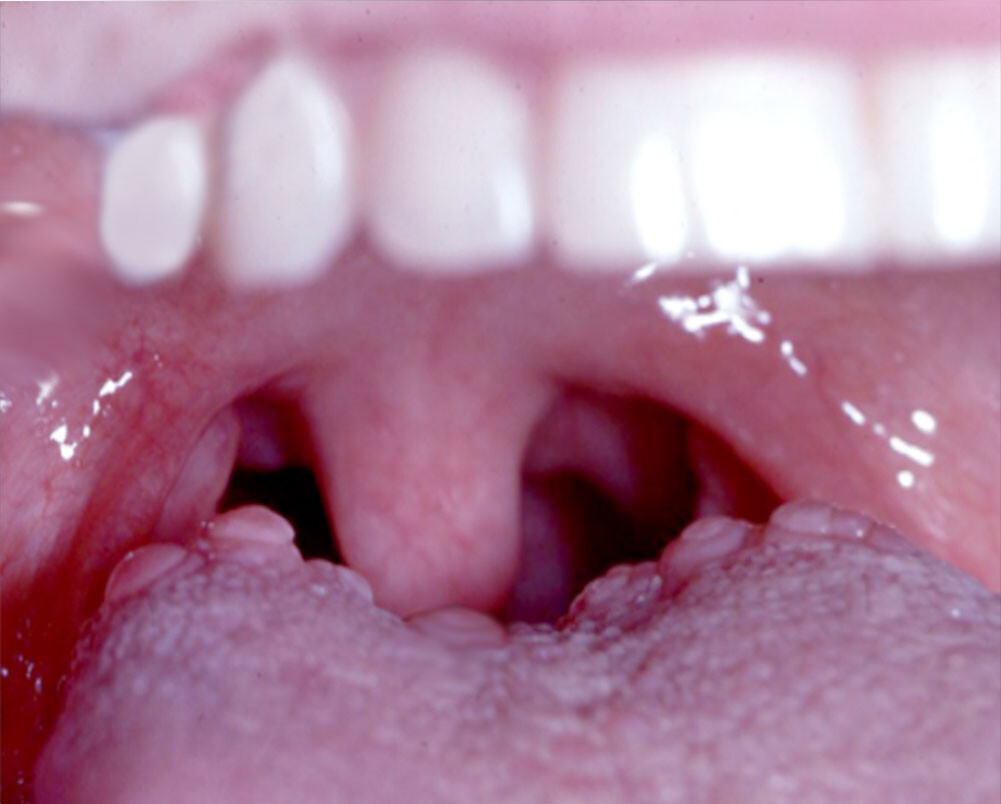

The tongue is made up of muscles and the surface is covered with a mucous membrane. Typically, small bumps (also known as papillae) cover the surface of the back part of your tongue. Between the papillae are your taste buds that help you taste foods. Usually, these papillae are pretty unnoticeable. But sometimes, they become enlarged and can cause you pain. This can happen for many reasons.

Oral squamous papilloma. This is a benign mass that appears on the border of the tongue. They are often attributed to the human papillomavirus (HPV). According to a study in the International Journal of Scientific Reports, the best way to remove them is through surgery. They’re also unlikely to recur, except in immunocompromised patients.